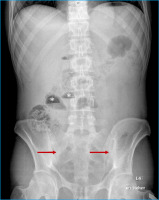

Dünndarmspiegel

Abbildung 2: Dünndarmspiegel (Sterne) als Zeichen des mechanischen Ileus. Nebenbefundlich Spondylitis ankylosans (Pfeil).

Keywords: IleusRöntgenbildSpondylitis